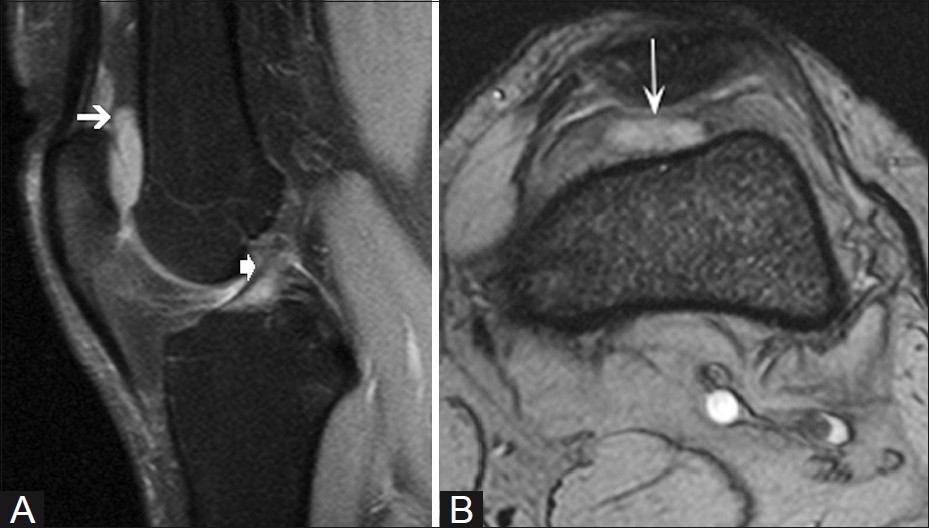

대부분의 정상적인 점액낭은 소량의 점액을 함유하여 MRI에서 잘 관찰되지 않지만, 염증성 변화에 의해 점액양이 증가되면 T1 영상에서 저신호 강도를, T2 영상에서 고신호 강도를 보이는 경계가 명확한 점액낭이 관찰된다.

△ 베이커 낭종(Baker's cyst)의 MRI 소견

치료는 그 원인에 따라 하여야 한다. 일반적으로 수술적 치료보다는 보존적 치료를 한다. 보존적 치료는 안정, 압박 붕대로 압박, 얼음 찜질(ice packs), 고정 등이 있다. 점액낭에 고여있는 삼출액을 뽑고, 외상성인 경우는 스테로이드를 국소 주사하고, 감염성인 경우는 균 검사를 하여 적절한 항생제를 선택하여 투여하며, 필요시 절개 배농을 시행해야 한다. 결핵성인 경우는 항결핵 치료제를 사용하여야 한다. 수술적 치료는 절개 배농 혹은 점액낭 절제술을 시행하고, 만성 점액낭염의 경우 골의 돌출이 있으면 뼈제거술을 시행할 수도 있다. 슬관절 강(Knee joint space)과 연결되는 점액낭염은 관절 내 병적 과정에서 영향을 받는다. 특히 슬와 낭종(poplteal cyst, 일명 Baker 낭종)은 소아에서는 관절내와 교통(communication)이 드물어 단순 절제술로 치유가 잘 되지만, 성인에서는 슬관절 후방부 활액막의 탈출(herniation)과 연관이 있으며 약 반수에서는 슬관절 내 병변, 즉 반월연골판 후각 손상이 있어 낭종 절제술만 시행하면 낭종이 재발할 수 있으므로 반드시 슬관절 내 병변의 유무를 확인하여 적절한 치료를 시행해야 한다.